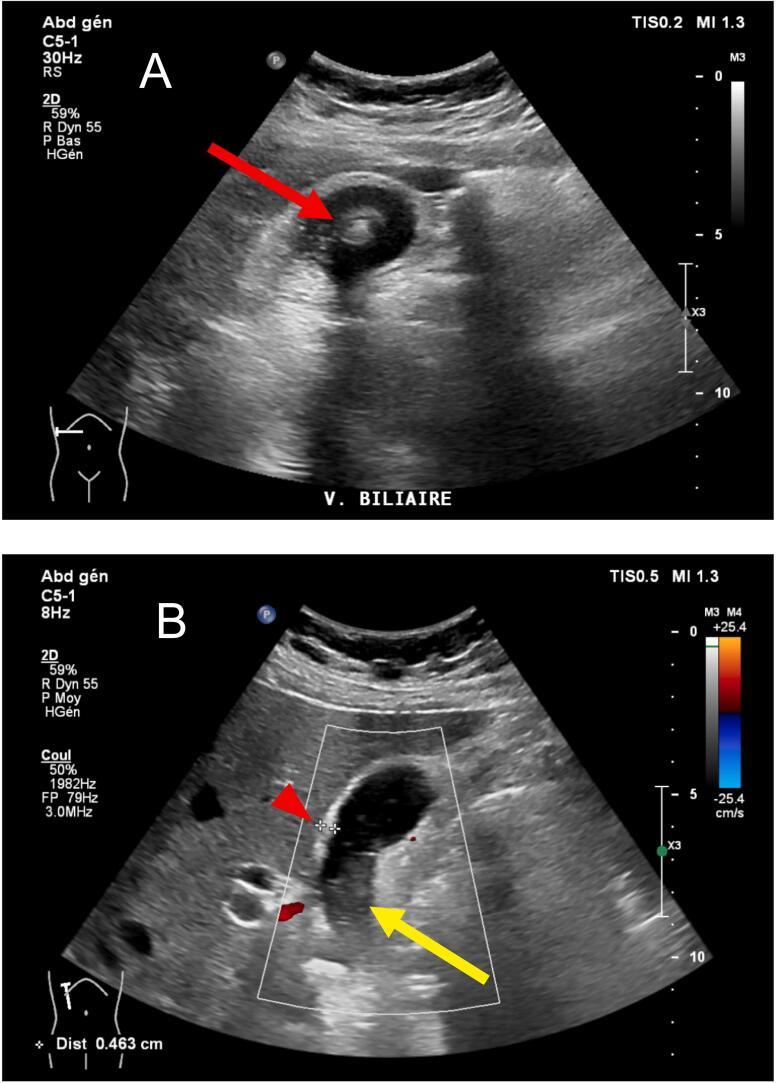

We report a case of a 51-year-old female with lithiasic cholecystitis showing areas of intestinal metaplasia associated with a mucocele. Laparoscopic cholecystectomy was performed with an uneventful postoperative course. Macroscopic findings revealed a dilated gallbladder filled with mucoid fluid. Signs of chronic and focally acute cholecystitis with areas of intestinal metaplasia were observed microscopically.

Lithiasic gallbladders can bear a gene that is found in goblet cells of intestinal metaplasia, leading to mucin hypersecretion. Metaplasia - a benign lesion often encountered on cholecystectomy specimens - can be the precursor of carcinoma. Mucin-producing gallbladder carcinoma is a very aggressive tumor that can appear as a mucocele. Consequently, preoperative computed tomography or magnetic resonance cholangiopancreatography should be performed in the presence of an unusual aspect on sonography.

我们报告一例51岁女性患有结石性胆囊炎,伴有与黏液囊肿相关的肠化生区域。行腹腔镜胆囊切除术,术后病程顺利。宏观检查发现胆囊扩张,充满黏液样液体。显微镜下观察到慢性和局灶性急性胆囊炎的迹象以及肠化生区域。

结石性胆囊可能携带在肠化生杯状细胞中发现的基因,导致黏蛋白高分泌。化生——胆囊切除标本中经常遇到的良性病变——可能是癌的前体。产生黏液的胆囊癌是一种非常侵袭性的肿瘤,可表现为黏液囊肿。因此,在超声检查出现异常表现时,应进行术前计算机断层扫描或磁共振胰胆管造影。